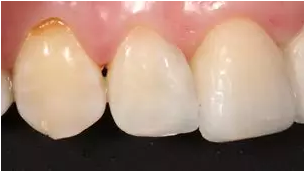

術(shù)前上前牙正面照

病例分享|復(fù)合樹脂微創(chuàng)美學(xué)修復(fù)關(guān)閉上前牙間隙